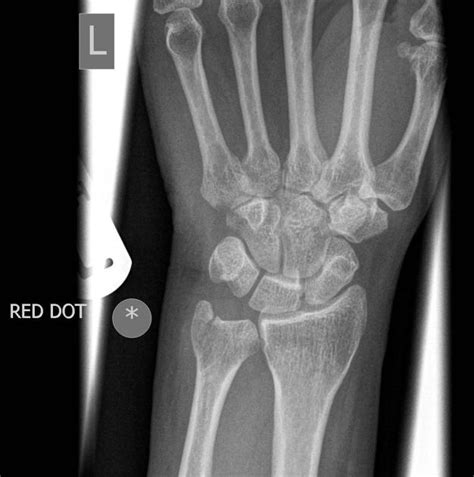

Diagnostic Approach

Diagnosing an ulnar styloid process fracture requires a comprehensive medical evaluation:

- Imaging studies including:

- X-rays

- CT scans

- Potentially MRI for soft tissue assessment